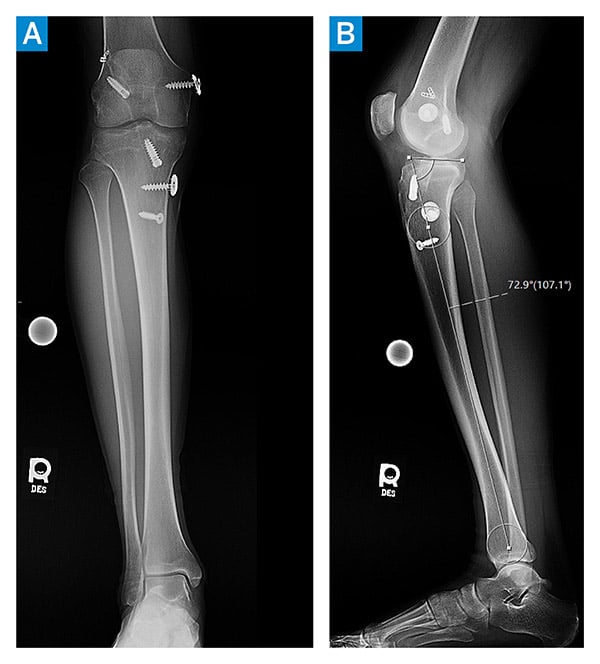

Physical examination demonstrated neutral alignment, a 3B Lachman test, and a grade-3 pivot shift. Collateral ligaments were stable with minimal medial opening to valgus stress. He lacked 2° to full extension and flexed to 135°. Preoperative imaging demonstrated increased posterior slope to approximately 17°, an absent ACL, and multiple fixation devices from his prior surgeries (Figure 1). A vertical tear in the posterior horn of the medial meniscus and an anterior subluxation of the tibia were noted (Figure 2). The articular surfaces were intact.

Figure 1: Preoperative right knee anteroposterior (A) and lateral (B) X-rays; (B) demonstrates a 17° posterior tibial slope.